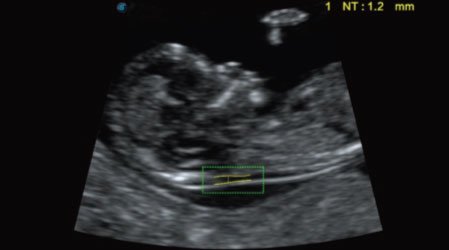

Auto NT

Auto NT provides semi-automatic, standardized measurements of the nuchal translucency thickness in 2D image and reduces operator dependency on the results.